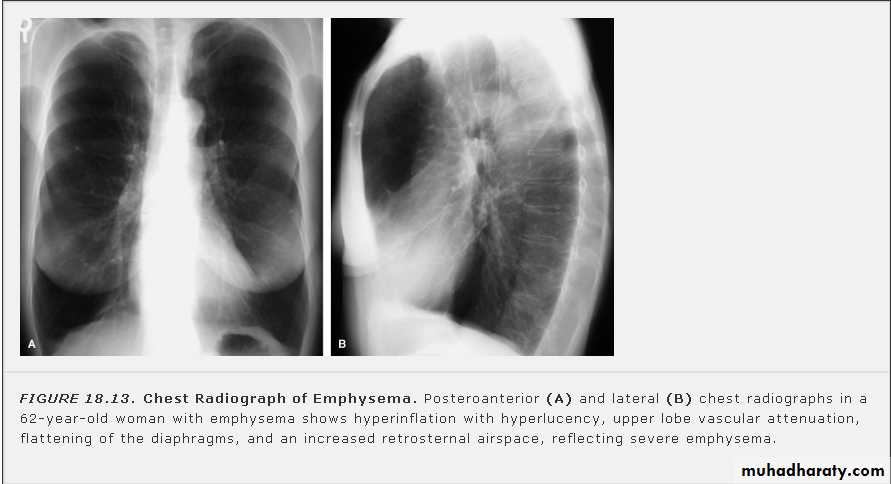

Pleural Effusion on Chest Radiographs.

Posteroanterior (A) and lateral (B) chest radiographs demonstrate the typical meniscoid appearance (arrows) in a patient with a left pleural effusion